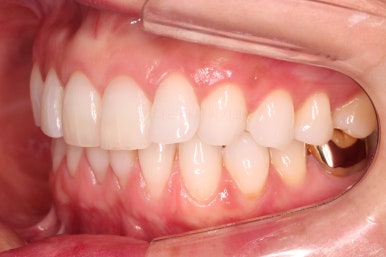

환자분이 원하시는 만큼 가지런해졌고, 부가적으로 생길 수 있는 부분들도 수용 가능한 선에서 잘 마무리가 되었습니다.

3개월이라는 빠른 기간 내에(심미보철 보다 약간만 더 긴 시간) 치아의 손상없이 마무리를 잘 했습니다.

물론 중간에 장치를 부착한 기간동안은 심미적으로 부담스러우셨겠지만요.

아래 앞니는 부분교정까지는 원하지 않으셔서 약간 다듬어 드리고 종료했습니다.